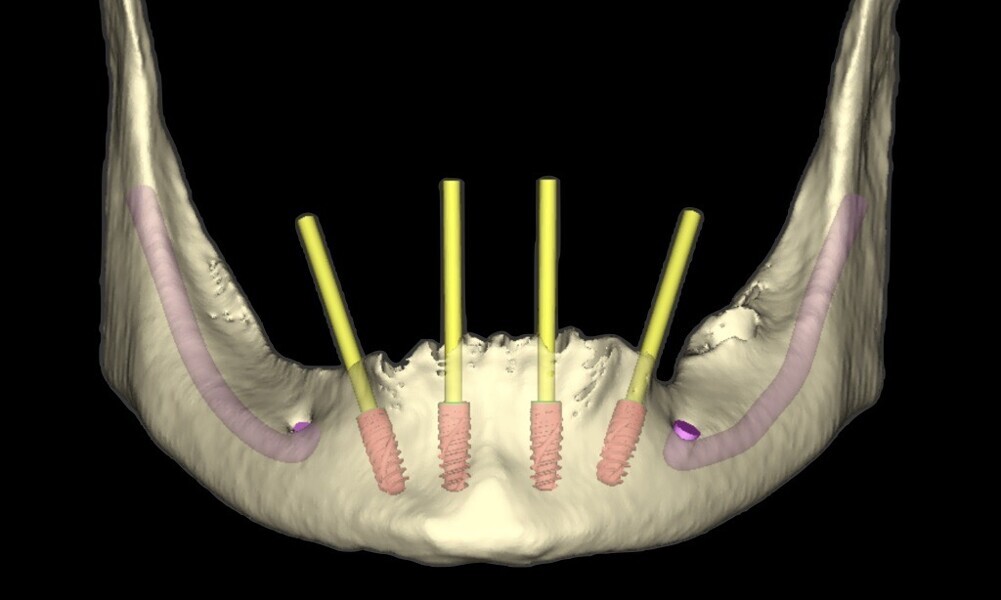

planning of implant positioning (18–21);

creation of a tooth- and mucosa-supported surgical guide to stabilise the drilling, ensuring accurate 3D positioning of the implants (22–28);

immediate implant placement in positions #34, 32, 42 and 44 using Straumann BLX implants (diameter: 4 mm; length: 10 mm);

Figs. 16–28: The treatment workflow included the extraction of hopeless teeth, implant planning and positioning, and surgical guide fabrication.

Fig. 18

Fig. 19

Fig. 20

Fig. 21